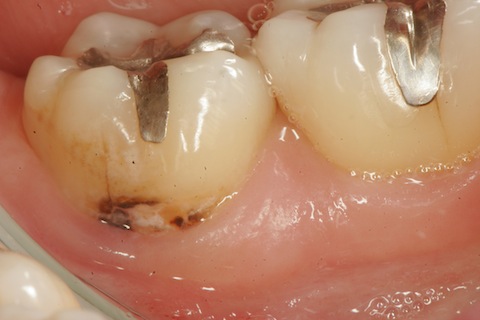

50代男性、右上5、6隣接面カリエス。冷水痛+。レントゲンで見ると、大きな虫歯に見えるが、肉眼ではそれほどでもない。エナメル質は全く溶けていないが、内部の象牙質だけが溶けている。この虫歯を見逃す歯医者はいないと思うが、なぜ象牙質だけが溶けるのか?という質問に答えられる歯医者は世界中探してもいない。できるのは僕だけwhttp://plaza.rakuten.co.jp/mabo400dc/diary/?PageId=11&ctgy=23歯はハイドロキシアパタイトというイオン電導性セラミックスが主成分で、電気(水素イオン)を通すことが知られていて、そのイオン化傾向を測ることもできる。http://plaza.rakuten.co.jp/mabo400dc/diary/201210150002/しかも象牙質の方がエナメル質よりわずかながらイオン化傾向が大きい。また、歯をpH3程度の酸性水溶液中に1ヶ月漬け込んでも溶けないが、外部から電圧をかけると簡単に溶ける。http://plaza.rakuten.co.jp/mabo400dc/diary/201210150000/これらのことから、この虫歯は象牙質とエナメル質を両電極とした局部電池が形成されることにより陰極となる象牙質だけが溶けると説明できる。ところが、世界中の歯医者はこのような虫歯を見慣れているが、なぜ、こういう虫歯ができるのかというのは知らない。ただ単に修復することができるだけだ。ところがCR充填すらできない歯医者は多い(というかほとんどだ)。なぜなら、世界中の歯医者は虫歯は細菌感染症だと思い込んでおり、虫歯を完全に除去しないと虫歯は再発すると信じ込んでいるからだ。このケースでは虫歯を完全に除去すると神経を取らざるを得なくなり、CR充填の適応症ではないと思い込んでいる。しかし、そうではない。虫歯を残しても、辺縁封鎖が完全なら、何の問題も生じない。要するに、虫歯があっても電気的に絶縁すればよいということだ。もちろん技術的な問題は大きいが。この症例のCR充填治療の所要時間は1時間。一回で終わり、神経も取らない、削って冠を被せるのも必要にならない。なんとコストパフォーマンスが高いことか!w